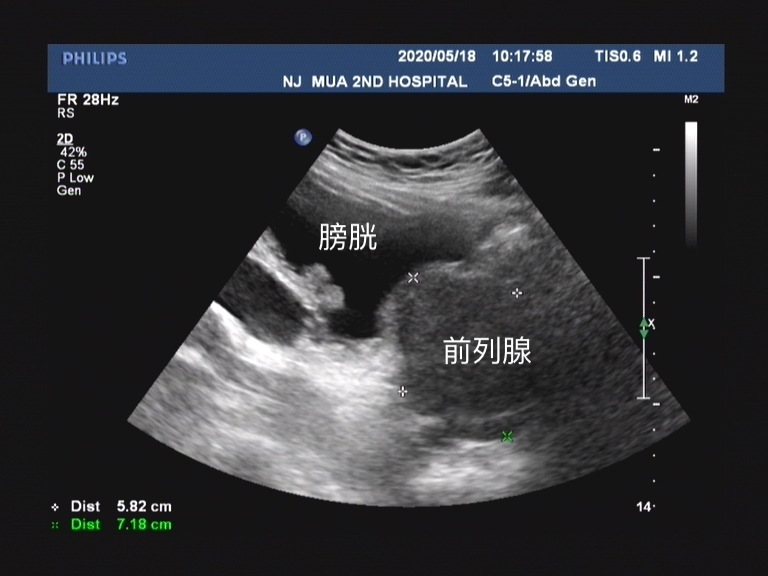

前列腺增生一直是让很多中老年男性头疼的排尿问题,不光 发病率高 ,对于男性的 生活质量也有非常大的影响 。在现阶段的临床工作中, 口服药物是很多患者的首选治疗方式 ,即使到了手术治疗的指征,但是 出于对手术的恐惧,和对手术并发症的恐惧,往往他们选择拒绝接受手术治疗。